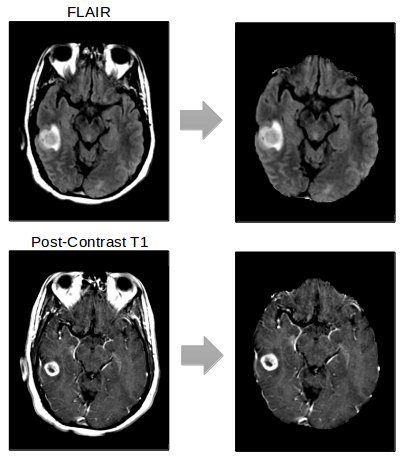

Standardized preprocessing methods are essential to deep learning pipelines that operate on medical images, as slight differences in preprocessing methods can lead to catastrophic prediction failures. DeepNeuro allows the user to preprocess data before inference using the Python object Preprocessor. Transformations applied in Preprocessor objects can be pure Python implementations, inference via neural networks, or links to outside programs such as 3DSlicer or ANTs [20]. These transformations can be applied to data held either in memory or loaded from a provided filepath, and can be returned as either Numpy arrays or stored back to disc. Preprocessors can be concatenated sequentially into preprocessing pipelines, or applied selectively to certain data objects and not others. Current Preprocessor objects available include 3D image registration (3DSlicer), 3D image resampling (3DSlicer), N4 Bias Correction (3DSlicer, ANTs), and skull stripping using a model trained with DeepNeuro (Figure 3).